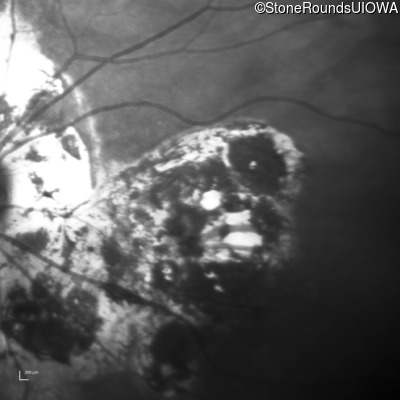

Infrared Fundus Photograph - Right - 20/160 -2

Exemplar